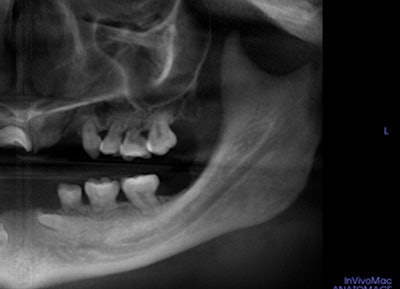

16-year-old girl with asymptomatic swelling

A 16-year-old girl presented to the oral surgeon, referred by her dentist, because of swelling affecting the left side of her face. The patient had experienced swelling for the past five to six weeks. A panoramic x-ray showed a lesion on the girl's posterior left mandible and maxilla.